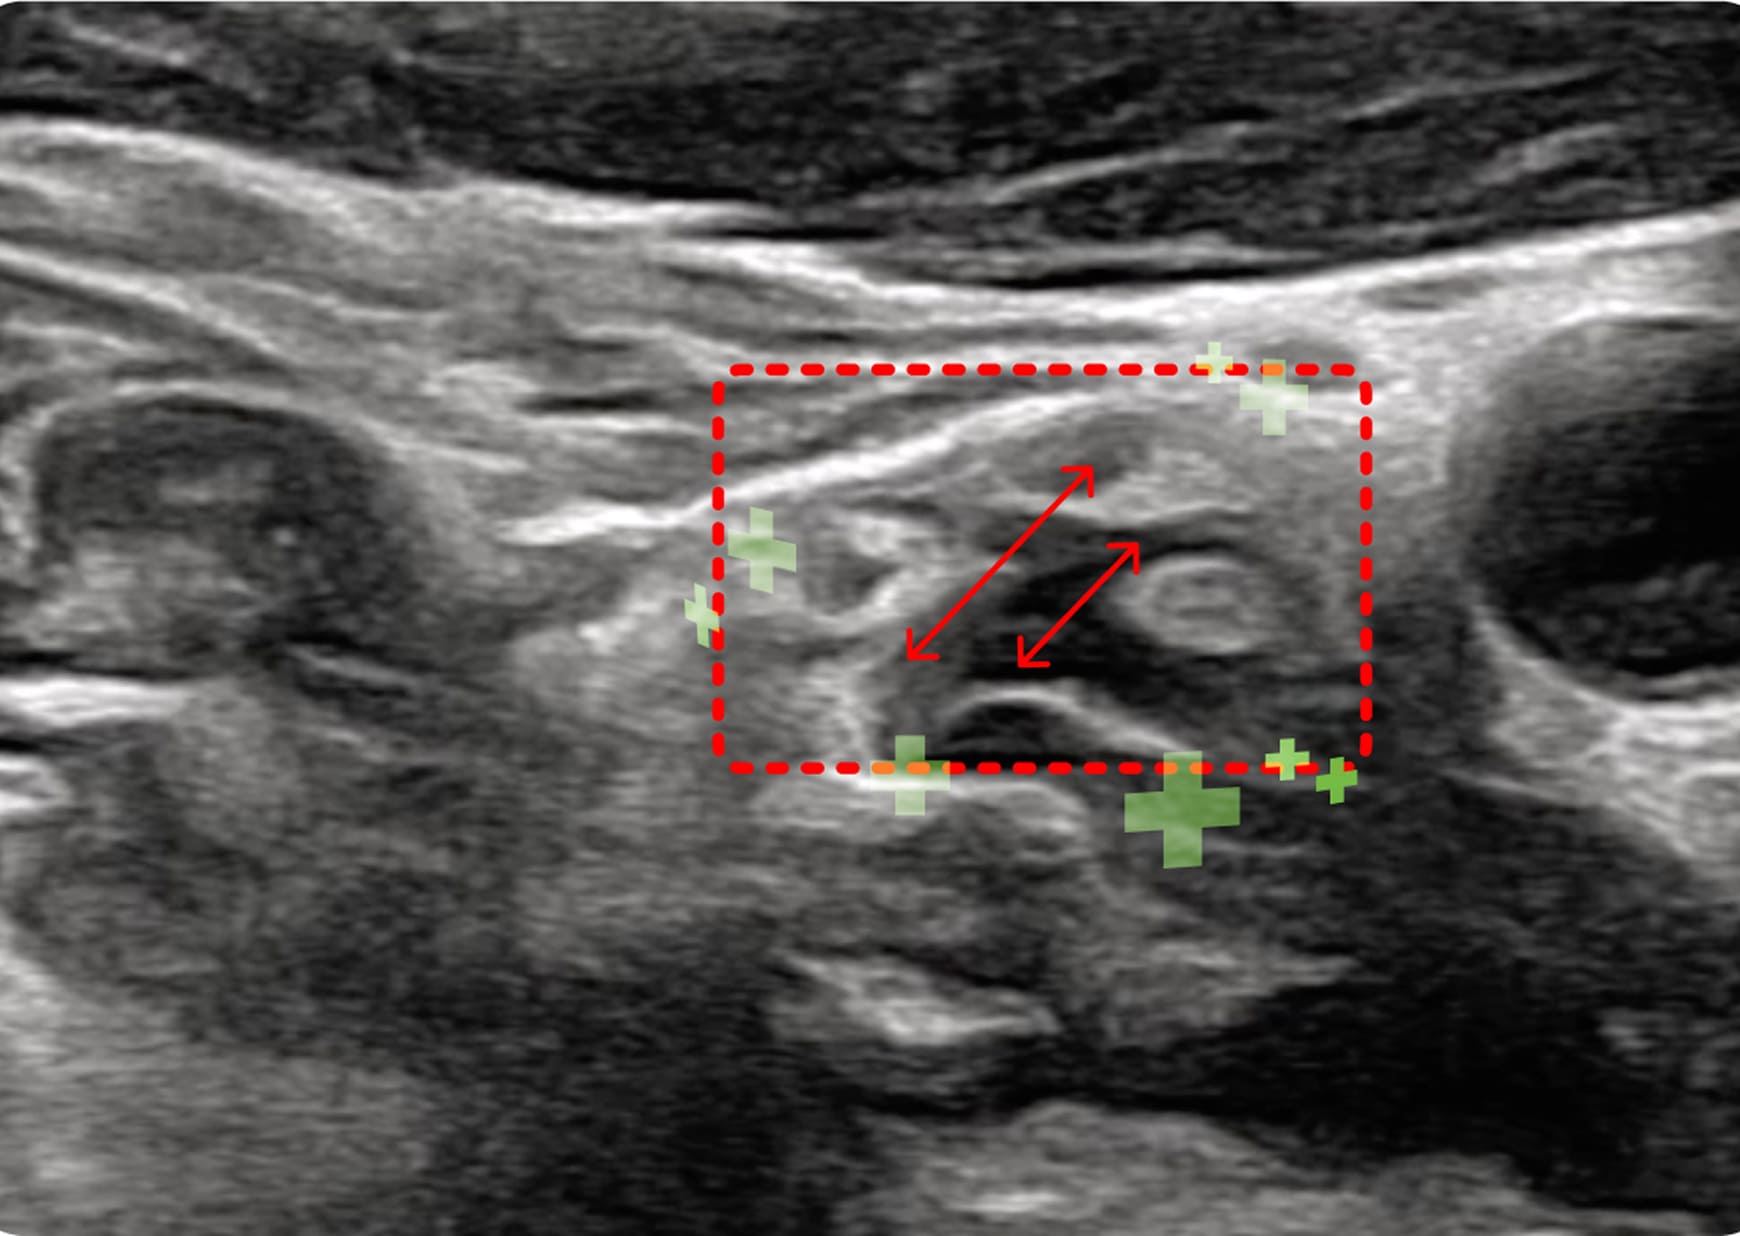

초음파 검사

1. 초음파 시술

초음파를 활용하여 근육과 신경 문제를

정확히 진단하고 치료하여 통증과 기능

이상을 개선하는 시술입니다.

익구개신경절, 악이복근

두면부의 자율 신경 신호와 림프 순환을 개선하여

이명, 돌발성 난청, 안구 및 구강 건조 등을 완화합니다.